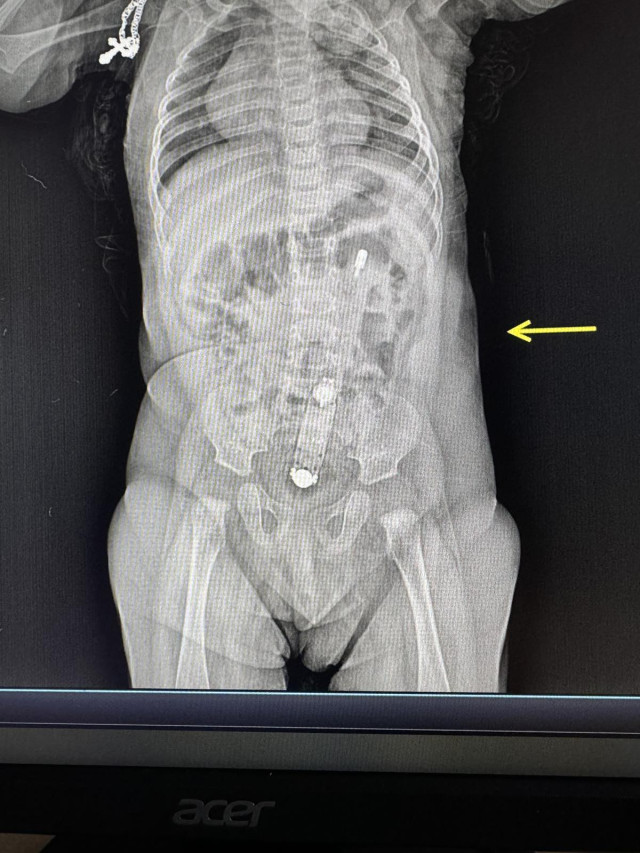

Вчора бригада екстреної медичної допомоги доправила у Волинське обласне медоб'єднання захисту материнства і дитинства із Каменя-Каширського маму із піврічною дитиною. Зі слів мами, у доньки закреп, тож вона намагалася зробити їй клізму за допомогою електронного термометра, змащеного олією, і він повністю опинився в товстому кишківнику дитини.

«На рентгені було чітко видно термометр, також він пальпувався через живіт. Дістати прилад було дуже непросто. Зробили це ендоскопічно, діяти треба було дуже обережно, щоб не травмувати немовляті анус та внутрішні органи. Самостійно градусник вийти не міг, натомість міг перфорувати кишківник або надалі спровокувати кишкову непрохідність», – розповідає хірургиня та ендоскопістка Волинська обласна дитяча клінічна лікарня Юлія Артишук.